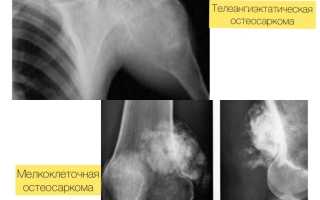

| Остеогенная саркома | Опухоль тазобедренного сустава возникает в результате перерождения костной ткани. Диагностируется чаще у детей мужского пола в возрасте от 5 до 15 лет. Характеризуется быстрым развитием и образованием метастаз в легких, печени. |

| Рентгенография | Обследование помогает выявить патологические изменения в тканях и костных структурах. |